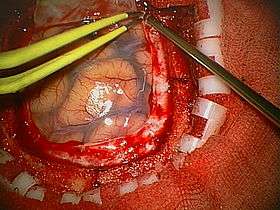

A craniotomy is a surgical operation in which a bone flap is temporarily removed from the skull to access the brain. Craniotomies are often critical operations, performed on patients who are suffering from brain lesions or traumatic brain injury (TBI), and can also allow doctors to surgically implant deep brain stimulators for the treatment of Parkinson's disease, epilepsy, and cerebellar tremor.

The procedure is also widely used in neuroscience for extracellular recording, brain imaging, and for neurological manipulations such as electrical stimulation and chemical titration. The procedures are used for accessing brain tissue that must be removed, as well.

Craniotomy is distinguished from craniectomy (in which the skull flap is not immediately replaced, allowing the brain to swell, thus reducing intracranial pressure) and from trepanation, the creation of a burr hole through the cranium in to the dura mater.

Human craniotomy is usually performed under general anesthesia but can be also done with the patient awake using a local anaesthetic; the procedure, typically, does not involve significant discomfort for the patient. In general, a craniotomy will be preceded by an MRI scan which provides an image of the brain that the surgeon uses to plan the precise location for bone removal and the appropriate angle of access to the relevant brain areas. The amount of skull that needs to be removed depends on the type of surgery being performed. The bone flap is then replaced using titanium plates and screws or another form of fixation (wire, suture, etc.).